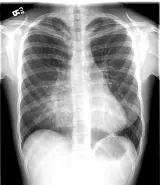

Over 2,100 interactive radiology cases, curated by radiologists for your level of training. Scroll, window, and view cases full screen — just like on PACS. Click linked findings in each writeup to jump straight to them on the image. Cases include sample reports, a focused discussion section, original illustrations, and videos.

PACSで期待されるツールを完備した完全インタラクティブな症例 — スクロール、ウィンドウ調整、ズーム、パン、計測、ROI、フルスクリーンモード。

重要な所見を症例画像上に直接ハイライトする豊富なアノテーション。症例解説内のリンクされた所見をクリックすると、スキャン上の正確な位置へジャンプできます。